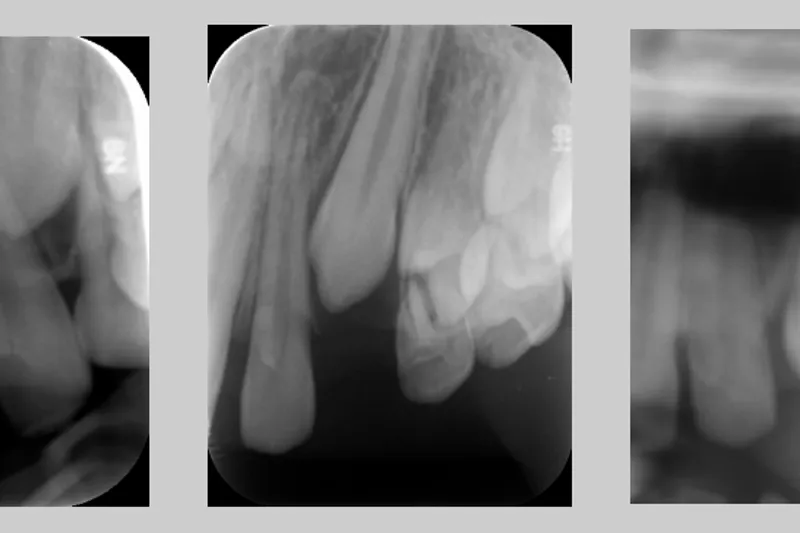

En gennemgang af litteraturen beskriver overordnet tre kirurgiske metoder til blotlæggelse af den retinerede hjørnetand: den åbne, den lukkede og den apikalt forskudte lapteknik. Der er ikke enighed om, hvornår den ene teknik bør benyttes frem for den anden, men det angives dog generelt, at det overliggende blødtvæv samt placering af den retinerede hjørnetand er afgørende for valget af teknik. Artiklen gennemgår de forskellige kirurgiske teknikker, og der beskrives komplikationer til den kirurgiske samt ortodontiske behandling som fx resorptioner, fæstetab og postoperative smerter.

A review of the literature generally describes three surgical methods for exposing the impacted canine: the open, the closed and the apically displaced flap technique. There is no consensus as to when one technique should be used in favour of the other, but it is generally stated that the overlying soft tissue and placement of the impacted canine is crucial for the choice of technique. The article reviews the different surgical techniques and describes complications for surgical and orthodontic treatment, such as resorptions, bone loss, and post-operative pain.